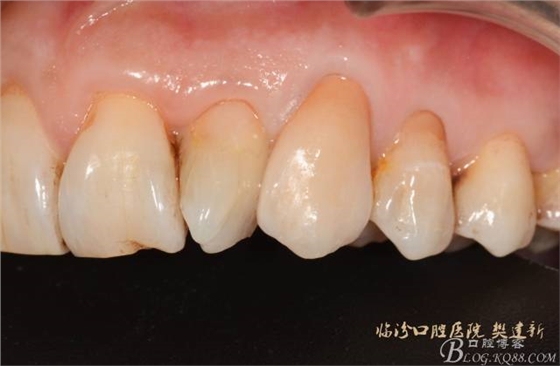

圖10修復(fù)體代入口內(nèi)照

圖12修復(fù)體代入口內(nèi)正面照